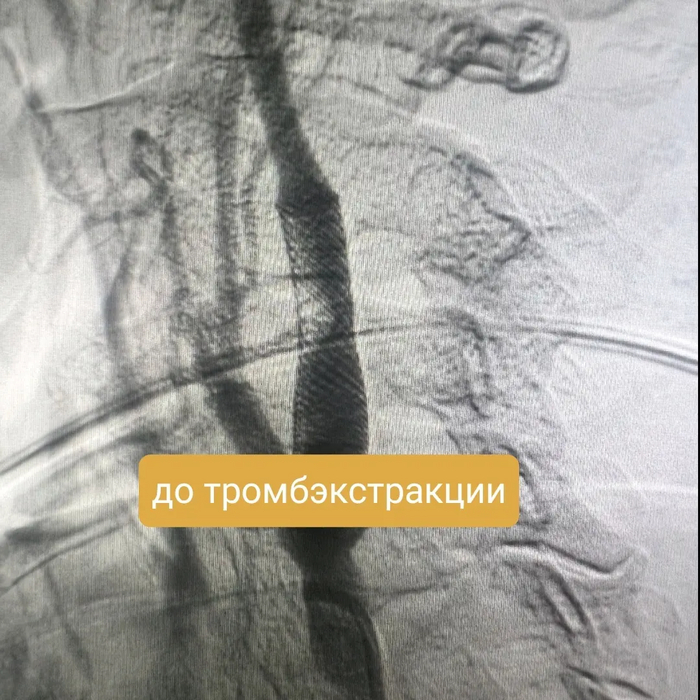

Итак на коронарографии такая картина при первой же съемке:

Стенозирование передней межжелудочковой артерии (ПМЖА) в начальном (проксимальном сегменте), инфаркты при полном закрытии ПМЖА в этом сегменте часто фатальные, либо приводят к инвалидизации

Оператор, с учетом такой картины, решает уточнить морфологию поражения, для выбора правильной тактики лечения (то что это нужно стентировать сомнений нет).